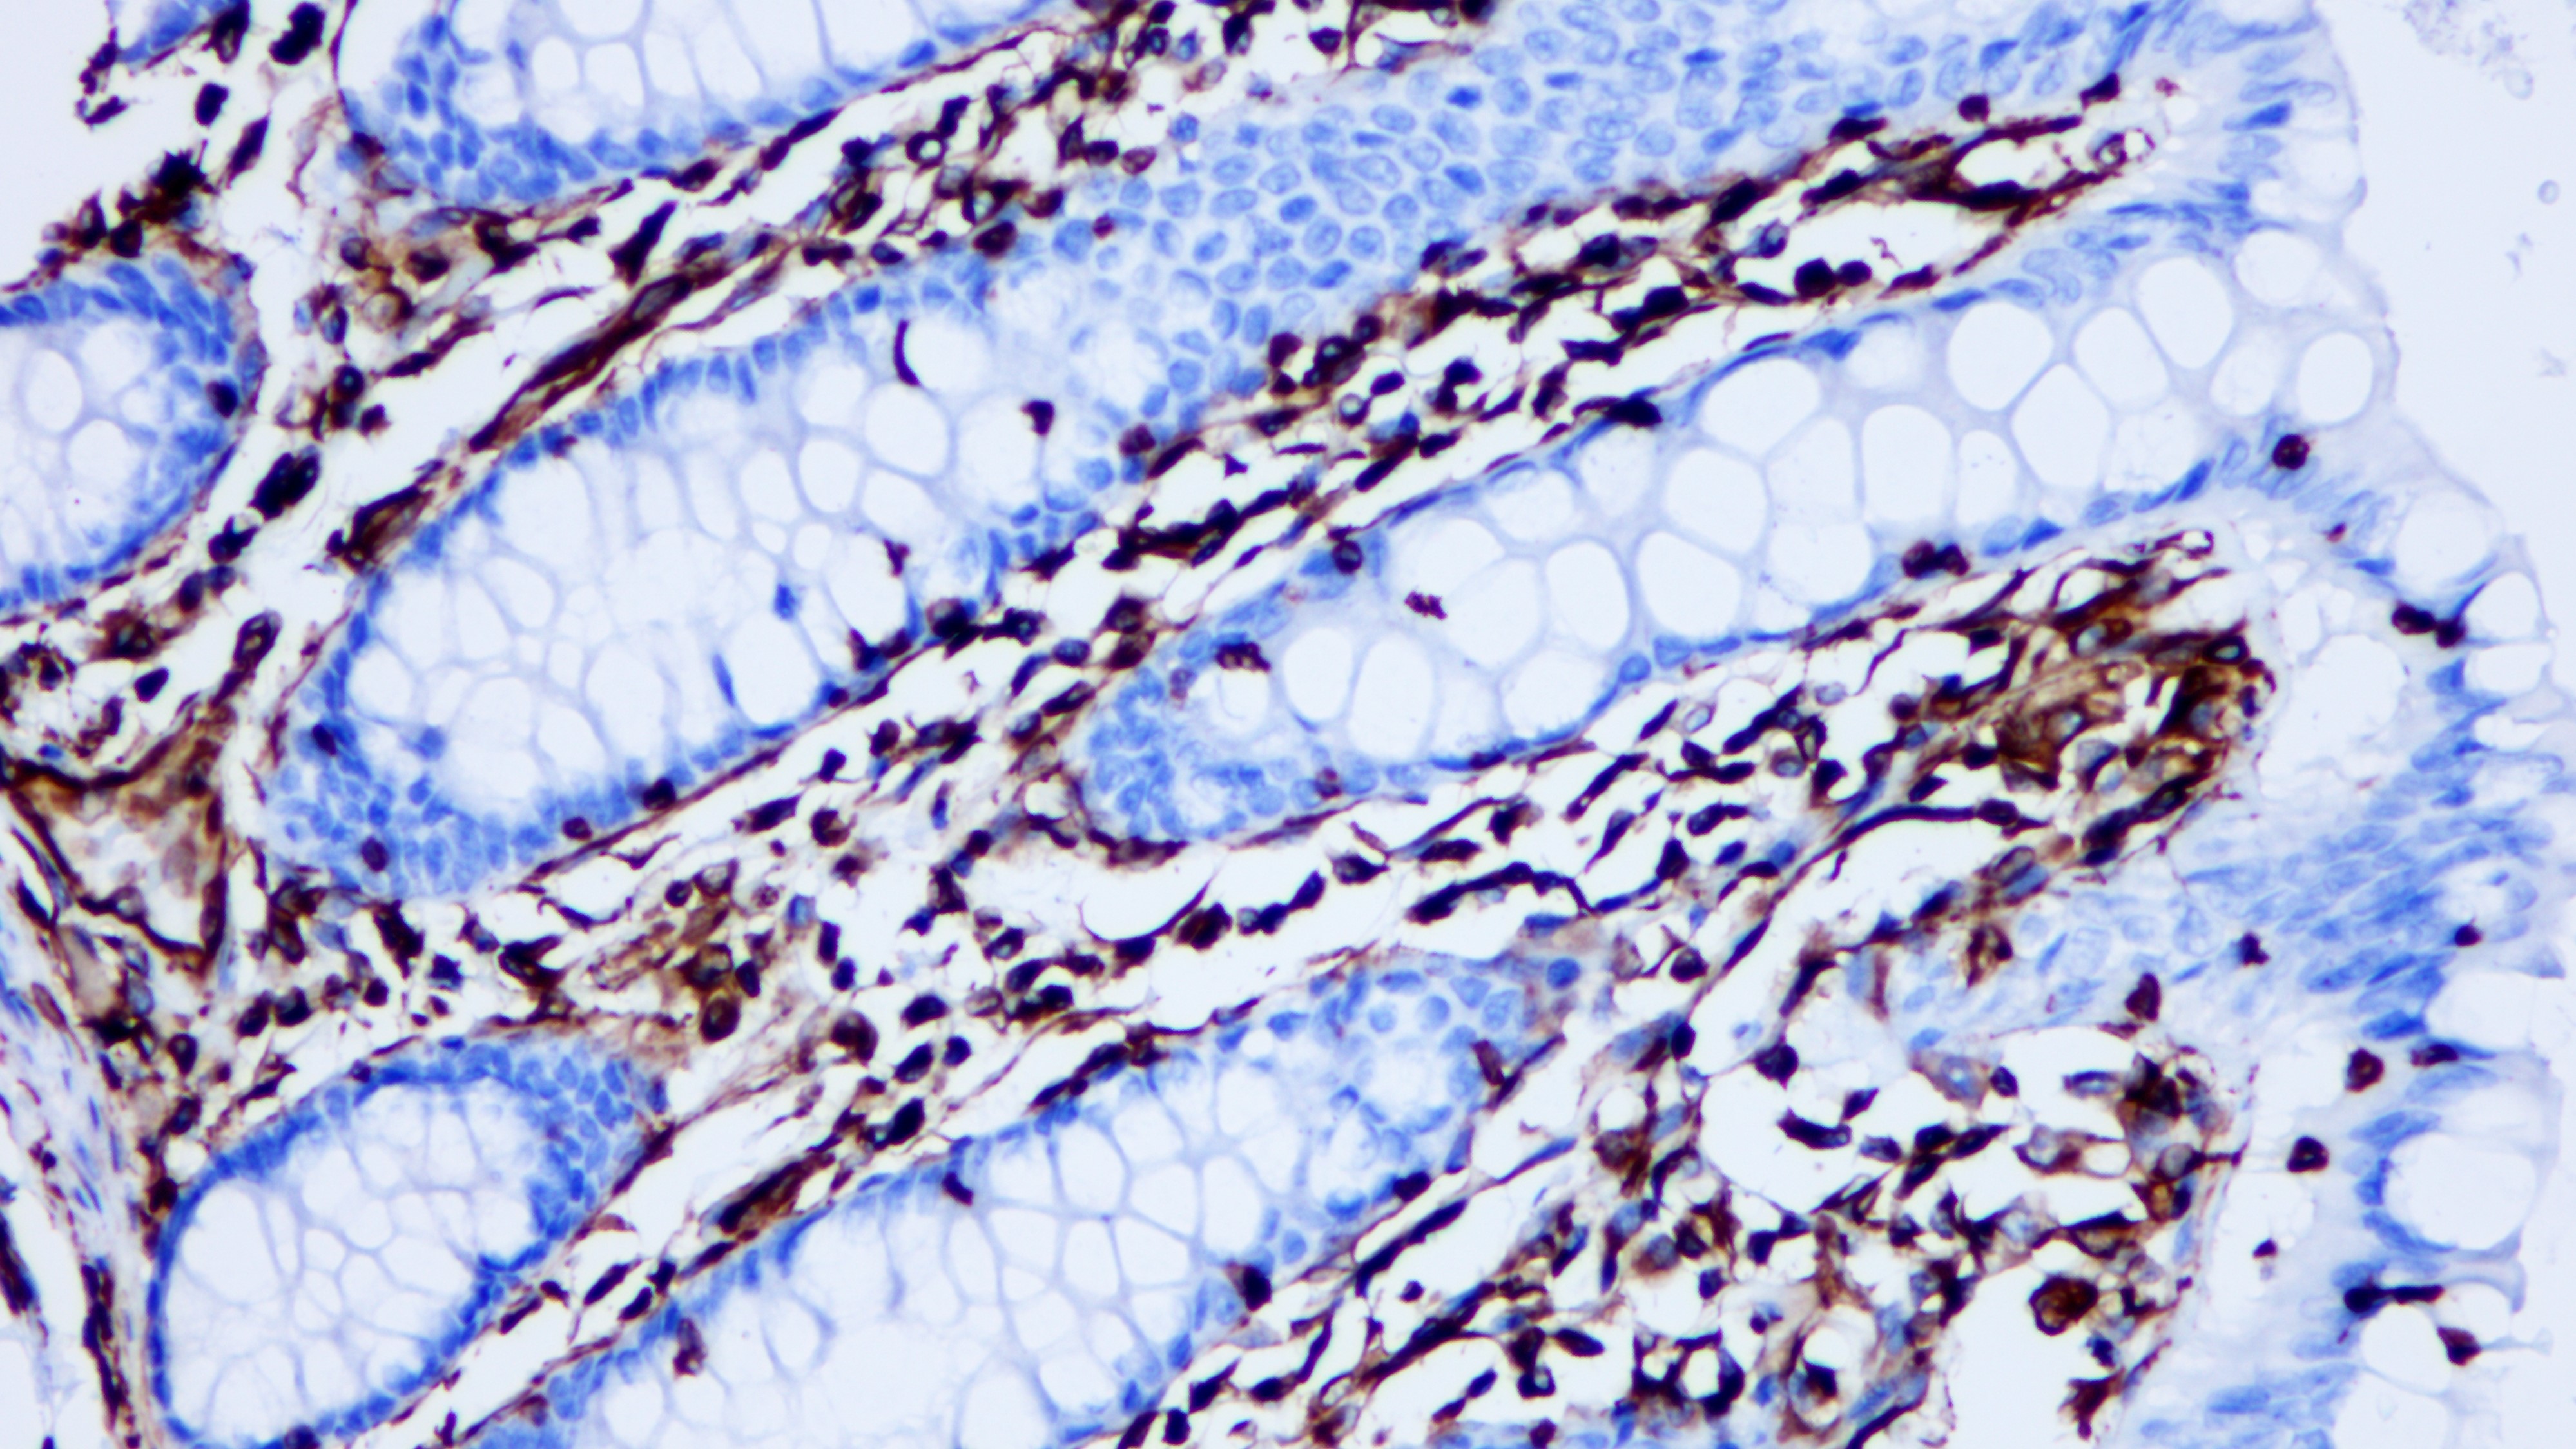

Vimentin(波形蛋白)是中间丝的其中一种蛋白,是真核生物细胞骨架重要组成成分,其对细胞的完整性和细胞骨架稳定性至关重要。Vimentin表达于多种间充质细胞类型:成纤维细胞、内皮细胞等,以及从中胚层衍生的许多其他细胞类型,如间皮瘤和卵巢颗粒细胞。但是,在非血管平滑肌细胞中Vimentin常被Desmin所替代。在肿瘤组织中,Vimentin存在于许多不同的肿瘤中,尤其是在那些起源于间充质细胞的肿瘤组织。Vimentin与其他抗体组合检测,用于鉴别间充质来源肿瘤和恶性黑色素瘤。此外,Vimentin可作为一种有效的组织处理标志物。

阳性对照

结肠